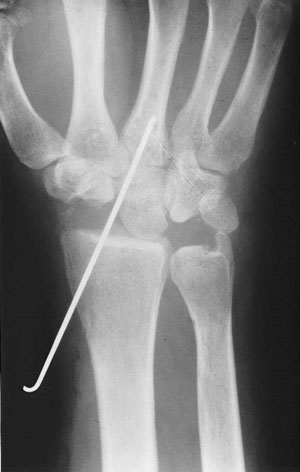

Radiografía simple.

La radiografía puede mostrar cambios en la densidad del semilunar, esclerosis, pérdida de altura, colapso o signos degenerativos en fases más avanzadas. También puede ayudar a identificar variantes anatómicas asociadas, como el cúbito corto.